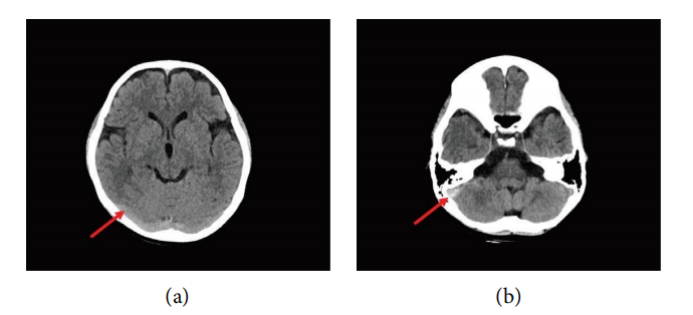

· 初次CT(回顾性分析):事后回顾伤后60小时的CT图像发现,右侧横窦和乙状窦区域存在高密度影(“高密度征”),这是静脉窦内急性血栓的早期征象。然而,这一细微的线索在初次阅片时被忽略,直接导致了诊断的延误。

· 诊断性MRI/MRV:入院后进行的MRI/MRV检查明确显示了右侧横窦、乙状窦及颈内静脉颅内段的血栓形成,表现为T1WI呈混杂信号,T2WI及FLAIR序列呈高信号,MRV上相应区域出现血流信号中断(充盈缺损)。